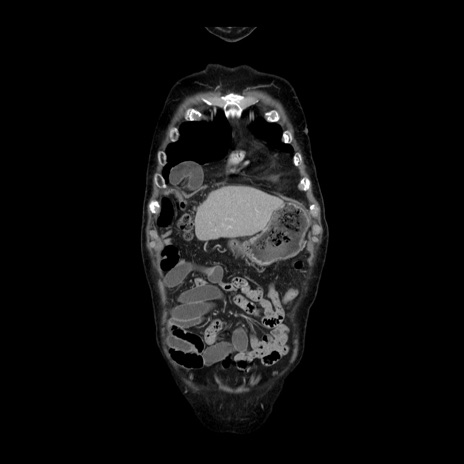

症例21(冠状断像)

【症例】70歳代男性

【主訴】腹痛

【現病歴】肝硬変・肝細胞癌にてかかりつけの方。約9時間前に食後より腹痛出現。症状が徐々に増悪し、嘔吐出現したため来院。

【既往歴】肝硬変、肝細胞癌(RFA、TACE後)

【身体所見】意識清明、表情苦悶様、BT 36℃、BP 129/78mmHg、P 88bpm、SpO2 97%(RA)、右上腹部から心窩部にかけて圧痛あり、反跳痛なし、筋性防御あり。

【データ】WBC 5800、CRP 0.16